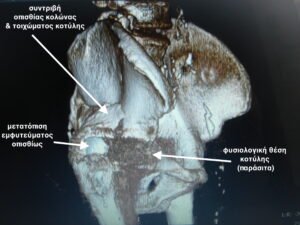

- Τρισδιάστατη αξονική τομογραφία (παράσιτα λόγω εμφυτεύματος) δείχνει την αποκόλληση του εμφυτεύματος της κοτύλης και την οπίσθια μετατόπιση του , μαζί με το κάταγμα του οπισθίου τοιχώματος της κοτύλης.

- Δυσδιάστατη ακτινογραφία όπου φαίνεται η μετατόπιση του εμφυτεύματος της κοτύλης και το σπασμένο οπίσθιο τοίχωμα.

- Το αποκολλημένο εμφύτευμα της κοτύλης, με ενσωματωμένο ολόκληρο το οστικό οπίσθιο τοίχωμα της κοτύλης , μετά την αφαίρεσή τους